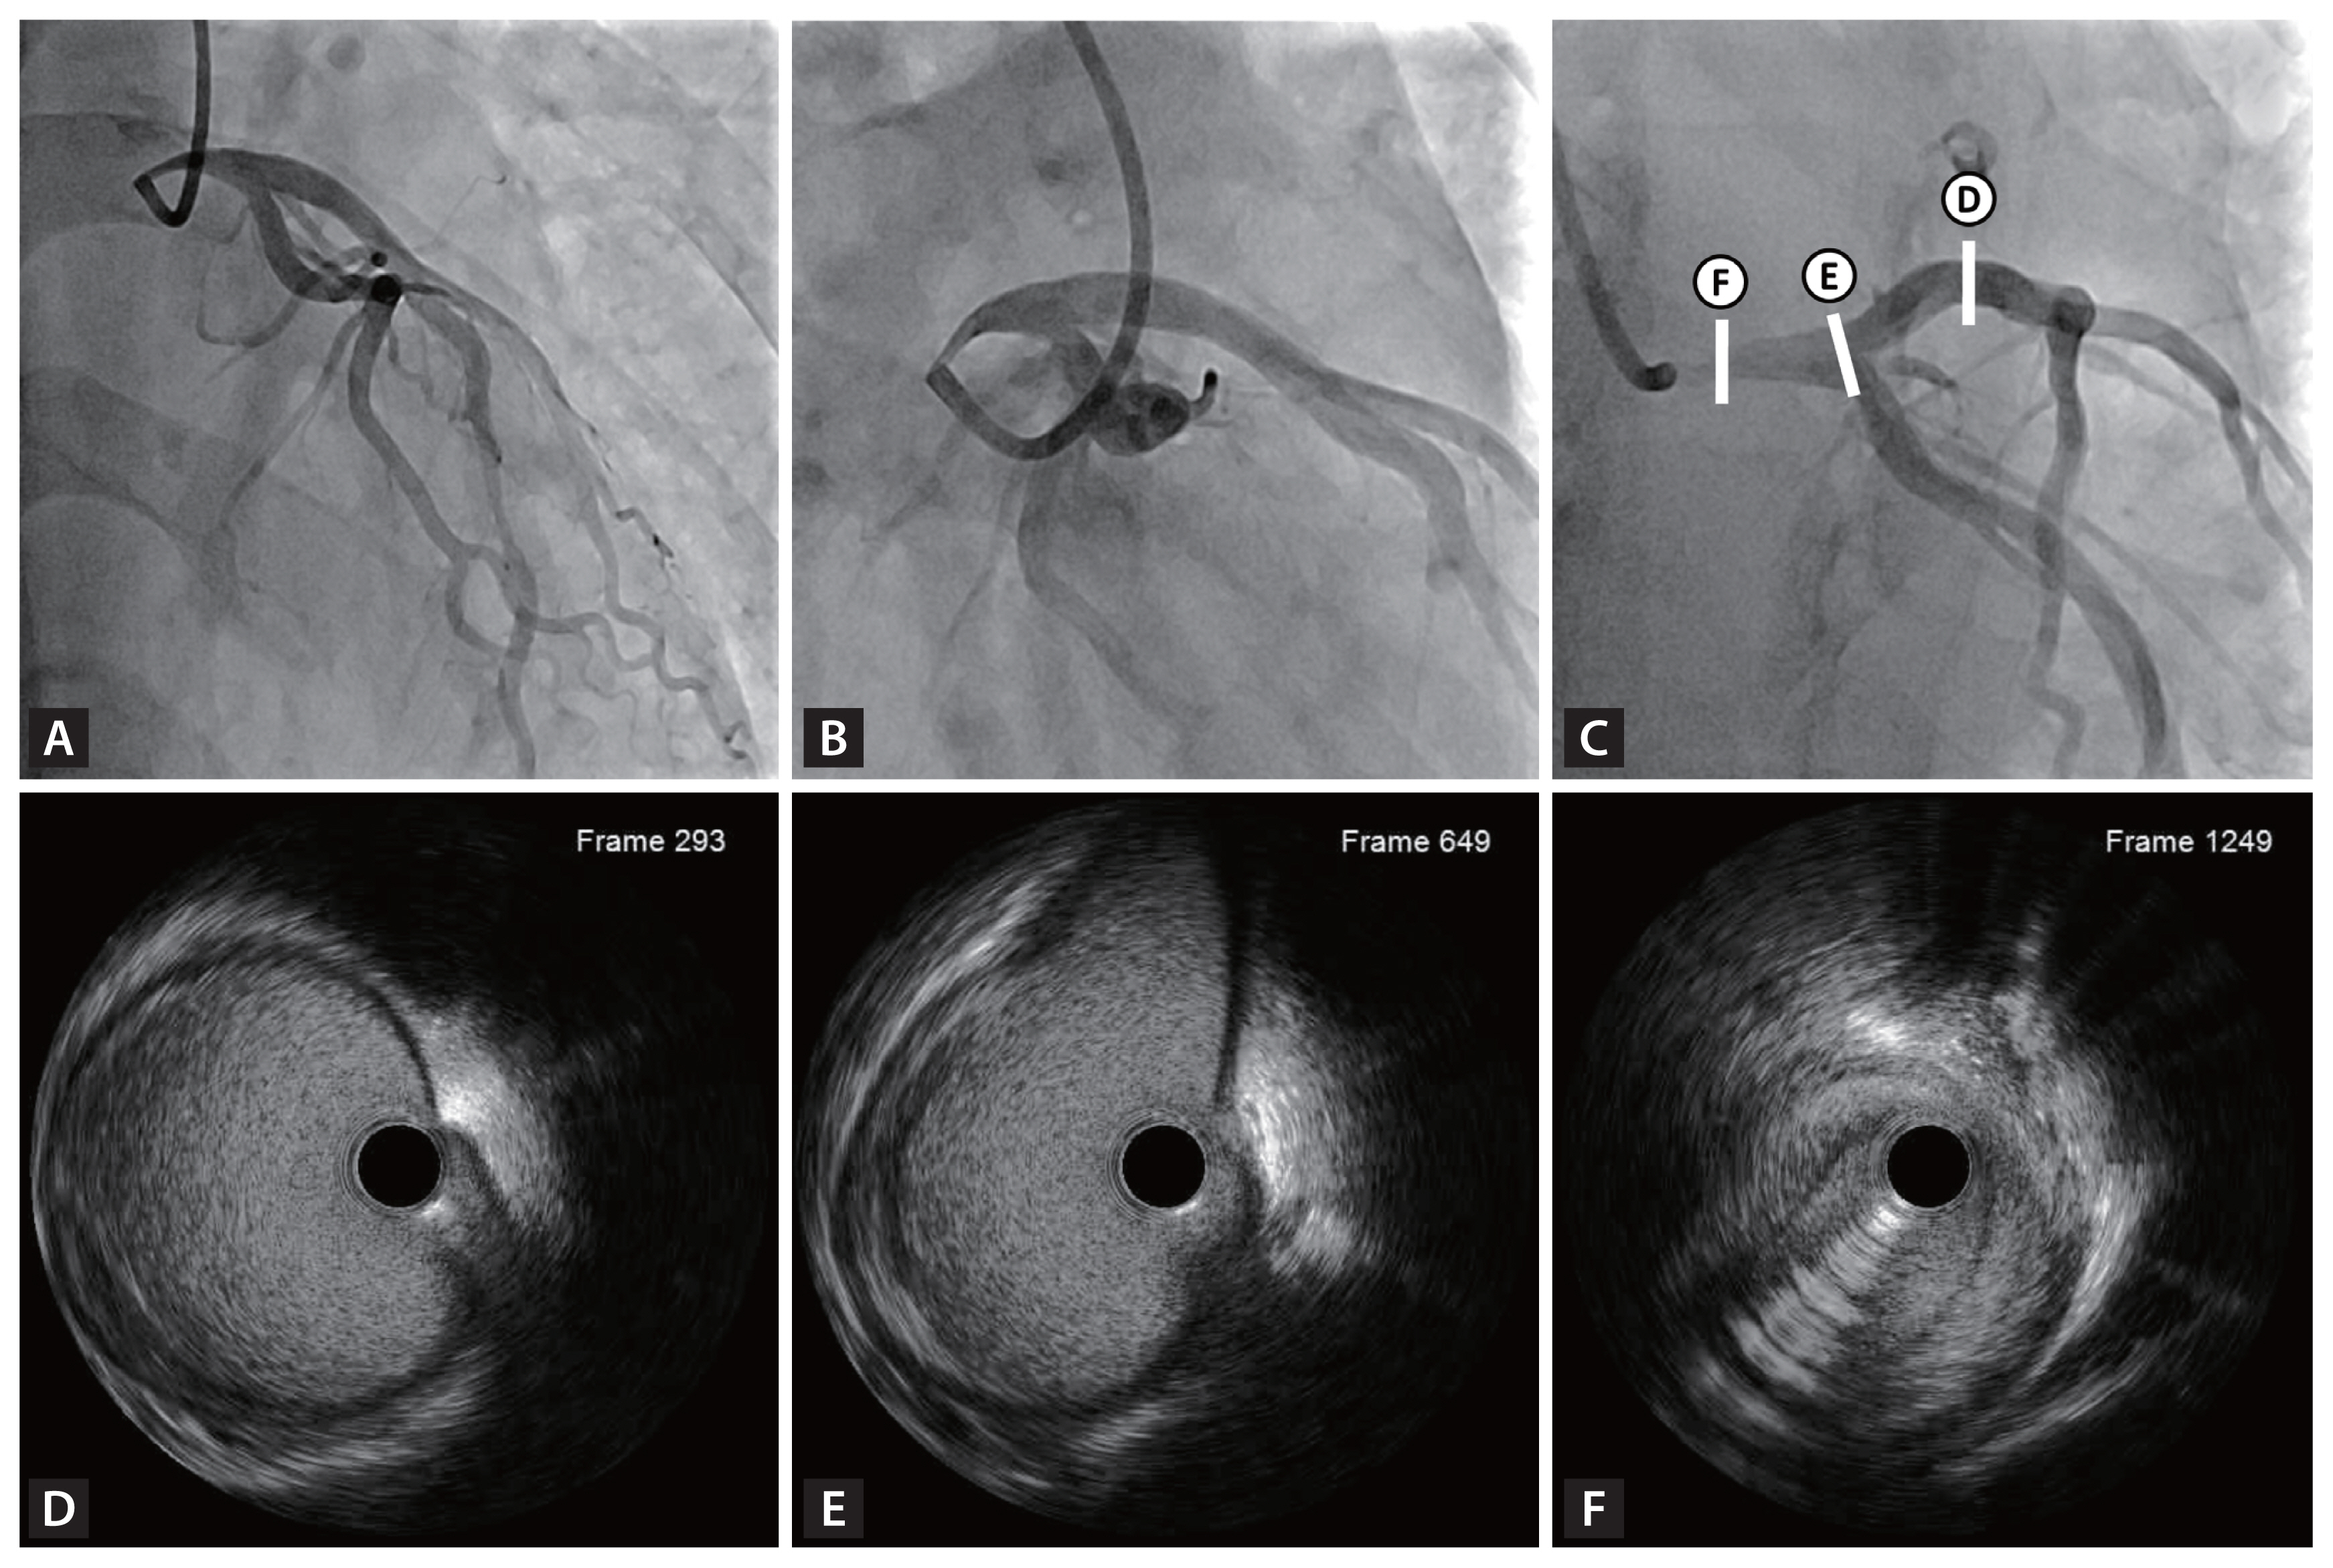

Figure 2

Coronary angiography and corresponding intravascular ultrasound (IVUS) images of the left coronary artery. (A, B) Coronary angiography revealed significant focal stenosis in the proximal left main artery, while the distal branches demonstrated preserved flow. (C) Coronary angiography with markers indicating the locations of IVUS cross-sectional images. (D, E) IVUS frames of the proximal left anterior descending artery and distal left main coronary artery show normal vessel anatomy without atherosclerosis. (F) IVUS frame of the proximal left main coronary artery demonstrates a luminal narrowing without significant plaque burden, likely due to external compression caused from anatomical deformity.

Electrocardiography and echocardiography results were within normal limits. However, cardiac computed tomography angiography revealed significant left main coronary artery (LMCA) stenosis due to an acute angle and relatively high takeoff of the LMCA, coursing between the aorta and pulmonary trunk (Fig. 1, Supplementary Video 1). Subsequent coronary angiography confirmed significant LMCA stenosis, and intravascular ultrasound demonstrated gradual narrowing of the proximal vessel lumen compared to distal reference, suggesting extrinsic compression rather than plaque accumulation. (Fig. 2). Considering the patient’s overall clinical assessment and multimodal imaging findings, he underwent coronary artery bypass graft surgery and recovered uneventfully.